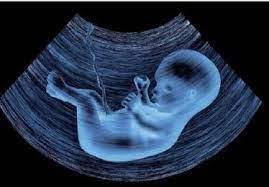

Πρόκειται για μια ακίνδυνη απεικονιστική μέθοδο, που χρησιμοποιεί ήχους υψηλής συχνότητας (υπέρηχοι), οι οποίοι με την βοήθεια προηγμένων τεχνικών, μετατρέπονται σε εικόνα. Η συμβολή των υπερήχων στην σύγχρονη παρακολούθηση τόσο της φυσιολογικής όσο και της επιπλεχθείσας εγκυμοσύνης, βελτίωσε και συνεχίζει να βελτιώνει σημαντικά την παρεχόμενη ιατρική φροντίδα στην έγκυο γυναίκα.

Ας δούμε, ακολούθως, ποια είναι τα βασικά υπερηχογραφήματα στην εγκυμοσύνη και γιατί πρέπει να είμαστε συνεπείς στη διενέργειά τους, προκειμένου να εξασφαλίσουμε την ασφαλή και ομαλή εξέλιξη μιας κύησης.

Πρόκειται για μία λεπτομερή υπερηχογραφική αξιολόγηση της ανατομίας του εμβρύου που πραγματοποιείται μεταξύ της 20ής – 23ης εβδομάδας της κύησης.

Το υπερηχογράφημα ελέγχει την ανατομία του εμβρύου (εγκέφαλος, πρόσωπο, σπονδυλική στήλη, καρδιά, θώρακα, στομάχι, έντερο, νεφρούς και άκρα), την θέση του πλακούντα, την ποσότητα του αμνιακού υγρού και την ανάπτυξη του εμβρύου. Εάν διαγνωστεί κάποια ανωμαλία, θα συζητηθεί με το ζευγάρι η σοβαρότητα της και η περαιτέρω αντιμετώπιση της κύησης. Τέλος, στο υπερηχογράφημα αυτό αξιολογούνται και δείκτες χρωμοσωμικών ανωμαλιών που μαζί με τα αποτελέσματα της αυχενικής διαφάνειας και του PAPP-A δίνουν την τελική πιθανότητα για χρωμοσωμικές ανωμαλίες.